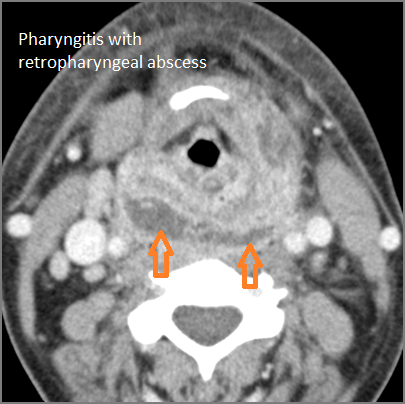

There is abscess within the adjacent deep neck, retropharyngeal and/or prevertebral spaces.